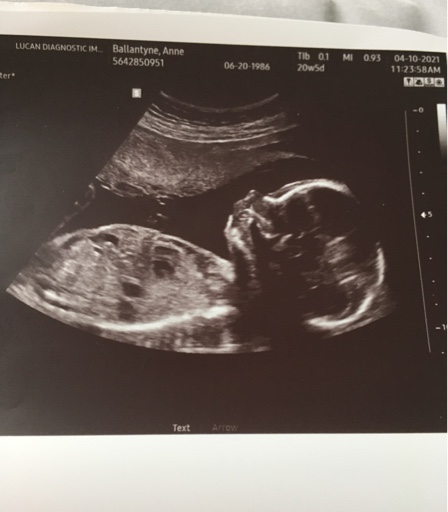

21 week pics of skull .... didn’t get any potty shots.

Attachment 43312

Attachment 43313